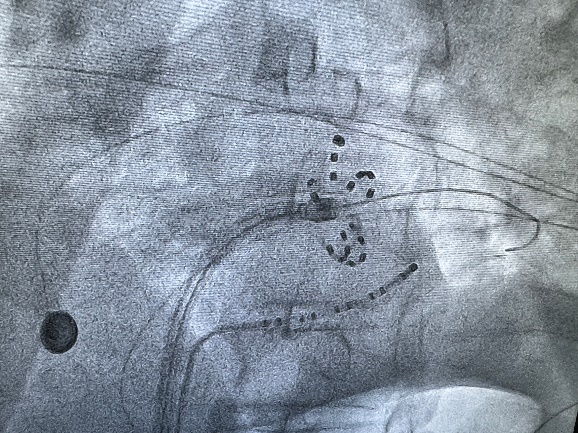

传统房颤消融多依赖三维标测系统,但青海大学附属医院团队凭借丰富的临床经验,在二维影像下精准完成了房颤脉冲消融,在肺静脉隔离的同时为患者个性化治疗,额外处理了三尖瓣峡部和上腔静脉区域。手术过程中,在三尖瓣第二个位置放电后,患者心律由房颤转为窦性心律,治疗效果立竿见影。整台手术消融时间仅30分钟,相较于传统消融手术,纯二维下脉冲消融时间显著缩短,手术无任何并发症或不良事件,展现了该院在复杂房颤治疗上的高水平技术与安全保障。

三尖瓣峡部消融时房颤转窦